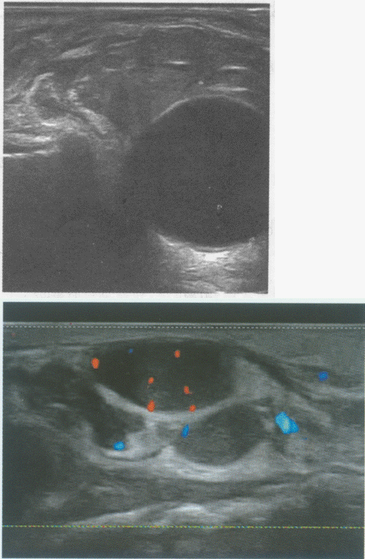

34、单项选择题

患者颈部肿大,可扪及肿块。如图,提示为()。

A.甲状腺腺瘤

B.结节性状腺肿大

C.甲状腺癌

D.甲状腺炎症

E.甲状腺囊肿

35、单项选择题